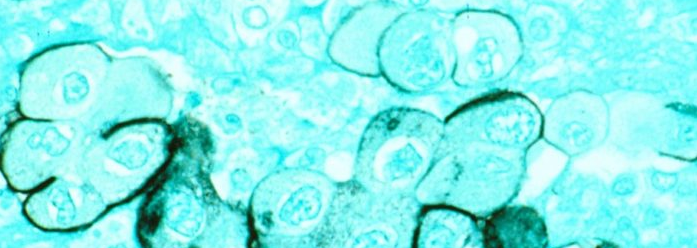

国立がん研究所(NCI)によると、焼けつくような痛み、チクチクする痛み、感覚障害、微細運動や体の位置や動きを知覚する能力の問題が、神経毒薬で治療されている患者の最大40%に影響を及ぼしているといわれています。神経障害を引き起こす可能性が最も高い薬剤は、オキサリプラチン (FOLFIRINOX 配合剤) などの白金系薬剤と、パクリタキセルなどのタキサン系薬剤です。神経障害が十分に重篤な場合は、治療計画を変更することができ、これらの薬剤はプロトコールから削除されます。

「神経障害は、オキサリプラチンやパクリタキセルなど、膵臓がんの治療に使用する化学療法剤の一般的な副作用です」と、ニューヨーク長老派病院/ワイル コーネル メディカル センターの消化器腫瘍専門医で臨床医学教授のアリソン オーシャン医学博士は言います。 「残念ながら、神経障害を予防する効果的なツールはなく、この症状を治療する選択肢は非常に限られています。」しかし、結局のところ、氷というシンプルで費用対効果の高い解決策がある可能性があることがわかりました。